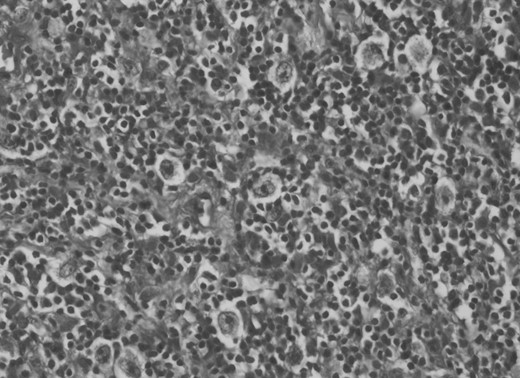

A 30-year-old male patient was admitted to our clinic with back pain. Pain was provoked by movements. The severity of pain was associated with the inability to perform the activities of daily living. The patient did not have any lymphoma-related B-type symptoms, including body weight loss, fever and sweat at night. He did not have a past and family history. There was no neurological deficit. Routine laboratory test results were normal. A magnetic resonance imaging (MRI) scan of the thoracic spine demonstrated an epidural tumor at the T9–11 level (Figs 1–3). The patient underwent spinal cord decompression via total laminectomy of T9–11 levels. Subtotal resection of the tumor was performed. Histological examination revealed the polymorphous cellular infiltration by histiocytes, large mononuclear cells and lacunar Reed–Sternberg cells with folded multi-lobed nuclei and small nucleoli (Fig. 4). Immunohistochemical staining was positive for CD15 and CD30 and negative for CD3, CD20, CD79a or CD45Ro. These features were most frequently observed in the mixed cellularity type of Hodgkin's lymphoma. Histological examination of the vertrebral body revealed no abnormality. The results of all other examinations (F-18 fluorodeoxyglucose positron emission tomography (F-18 FDG PET/CT), bone marrow biopsy and computed tomography (CT) of the chest, abdomen and pelvis) were negative for an occult disease. The patient was referred to the hematology department to undergo staged treatment. Six courses of chemotheraphy containing ABVD regimen (adriamycin, bleomycin, vinblastine and dacarbazine) were given to the patient. Postoperative MRI scan did not reveal any evidence of Hodgkin's disease (Fig. 5), F-18 FDG PET/CT, CT of the chest, abdomen and pelvis were obtained in 24 months and did not reveal any evidence of Hodgkin's disease.

Histological examination revealed mixed cellularity type of Hodgkin's lymphoma.